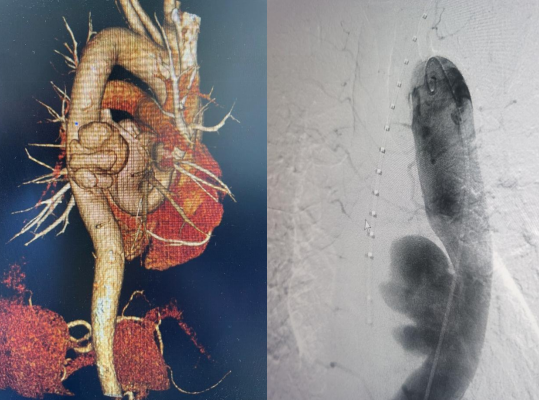

近日,乐鱼手机站入口胸心外科收治了一名胸主动脉瘤患者。患者58岁,男性,6月前出现腰背部疼痛不适,症状持续不缓解,多次就诊于当地医院。完善相关检查未见明显异常,给与止痛药物口服对症治疗,症状较前稍缓解。期间,上述症状间断发生。2周前,患者腰背部疼痛转移到胸背部疼痛,继而向前胸部扩展,疼痛无法耐受,就诊于市中心医院。入院后,胸主动脉CTA检查提示“胸主动脉瘤”,大小4.5x6.4x6.8cm,破口上下径2.8cm,胸心外科以“胸主动脉瘤”收治进一步治疗。

经过胸心外科、介入科、麻醉手术室、超声科多学科协作,于11月4日下午4点在急诊局麻下行胸主动脉覆膜支架夹腔内隔绝术,术中精准释放覆膜支架,复查血管造影显示,封闭主动脉破裂口,无内漏,支架位置良好,术区相关动脉血管显影良好,“不定时炸弹”成功拆除。术后给予患者抗板、止痛、控制血压等相应治疗,患者目前恢复良好,已顺利出院。该手术的成功,充分体现了我院多学科积极协作的团队精神。